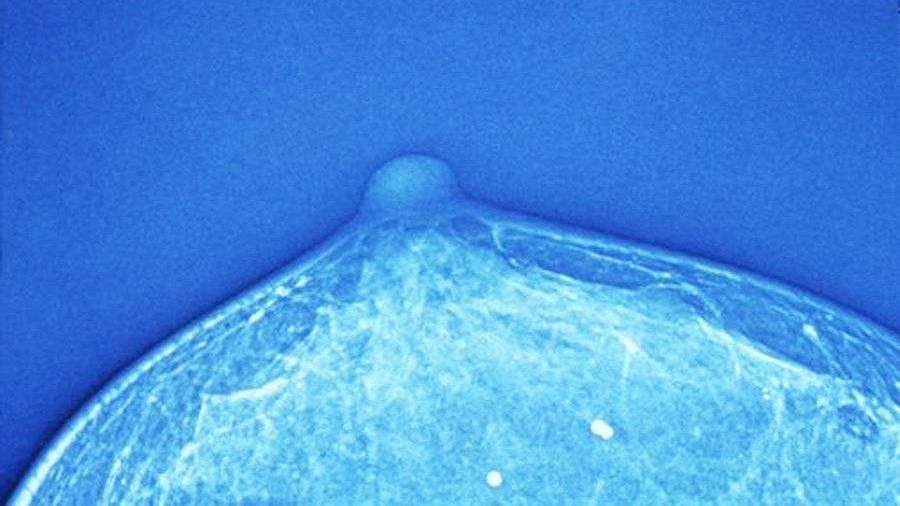

Фото: Global Look Press/Custom Medical Stock Photo

Ученые из Базельского университета (Швейцария) нашли вещество, помогающее остановить распространение метастазов при раке груди. Исследование специалистов опубликовано в журнале Cell.

Биологи отметили, что порядка 90% случаев летального исхода при онкологии связано с метастазированием (процессом образования вторичных очагов опухоли). В случае, когда метастазы поражают жизненно важные органы, спасти человека уже невозможно.

Для предотвращения распространения опасных клеток ученые провели масштабные испытания различных веществ и определили их влияние на циркулирующие опухолевые клетки (ЦОК).

Эти клетки попадают от очага заболевания в кровоток и, сбиваясь в кластеры, провоцируют появление метастазов.

При этом разложение кластеров может, наоборот, предотвратить их появление.

В работе авторы проанализировали 2486 соединений и обнаружили ингибитор Na +/K + ATPase, который разлагает кластеры ЦОК.

«Мы пытались найти подход борьбы с раком, который бы отличался от общепринятых. В итоге нашли препарат, который не убивает раковые клетки, но разобщает их», — рассказал руководитель исследования Никола Ацето.

Испытания проходили на лабораторных мышах. Теперь ученые хотят испытать вещество на пациентках с раком молочной железы.